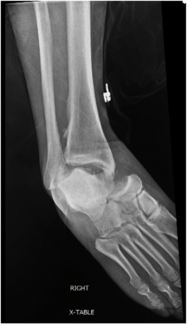

This author discusses decision-making regarding the syndesmosis, fixation choice, the best pathway for a posterior malleolar fragment, and fixation for the medial malleolus.

04/04/2024

Podiatry Today